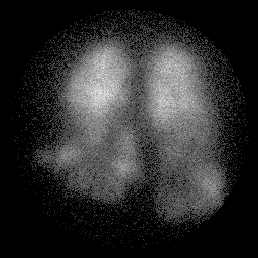

Example of COAD

L Post Oblique Perfusion L Post Oblique Ventilation

match_perf2.gif (20587 bytes) match_vent2.gif (15469 bytes)